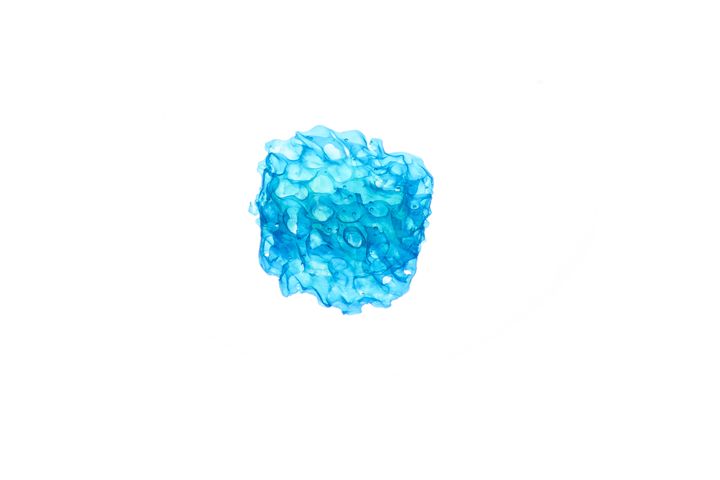

Precise Bio Reveals Scalable 3D Bioprinting Process After First Human Cell-Printed Cornea Transplant

A company has deployed a scalable process to 3D print human corneas.